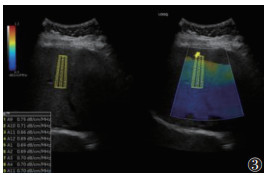

1.2 仪器与方法615例均行超声检查,采用GE20彩色多普勒超声诊断仪。受试者取仰卧位,伸展右上肢至头部,充分扩展肋间隙。选用凸阵探头(频率2~5 MHz),垂直放置探头,通过肋间隙对肝Ⅴ段行常规超声检查,并根据肝脏回声强度、肝肾回声对比、肝内血管和膈肌的清晰度,判断脂肪肝程度(无、轻度、中度和重度)[4];测量内脏脂肪厚度(visceral fat thickness,VFT),将探头置于脐上1 cm,测量双侧腹直肌间腹白线至腹主动脉前壁的距离[5](图 1),结果取双侧平均值。使用线阵探头(频率2~9 MHz)测量皮下脂肪厚度(subcutaneous fat thickness,SFT):将探头置于脐上1 cm,左右移动探头测量腹部两侧皮肤至腹直肌外缘距离(图 2),最终结果取双侧平均值[5]。激活UGAP模式,嘱患者屏住呼吸3~5 s,记录不同帧上连续回波UGAP-AC平均值,注意避开胆管、血管等伪影(图 3)。

| 注:蓝色代表该区域图像质量良好,测量时取样框尽量位于该区域内;红色代表该区域图像质量欠佳,测量时应避开 图 3 肝脏超声衰减参数(UGAP)声像图 |